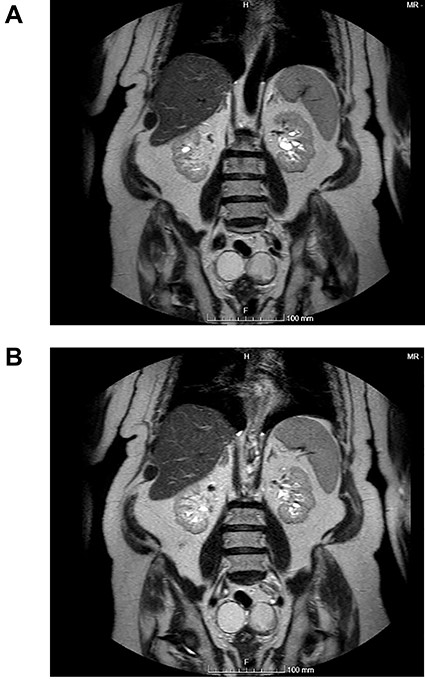

(A and B) Axial images of CT scan showing in the right ovary, a solid mass with predominantly fat density of 55 mm; and in the left ovary, a predominantly cystic mass of 65 mm.

The authors report the case of an asymptomatic 76-year-old female patient, referred to our Gynaecologic Clinic, due to suspicious adnexal lesions on a pelvic ultrasound (US). Menopause occurred at age 53. She had no history of abnormal uterine haemorrhage. Her menstrual cycles had been regular. She had had three gestations: two late abortions and one normal delivery, after which she breastfed. At our clinic, upon examination, vulva, vagina and cervix had no apparent lesions. The vaginal US revealed a right adnexal avascular cystic lesion of 65 mm, a left adnexal hyperechogenic cystic lesion of 60 mm, a normal sized uterus, a diffusely heterogeneous myometrium, an endometrial thickness of 8 mm and heterogenous intracavitary liquid. Her risk of ovarian malignancy assessment (ROMA) score was 28.1%, for a cut-off of 25.3%. Cancer antigen (CA) 125 and Human epididymis protein 4 (HE4) were 25.9 and 98.2, respectively. Lactate dehydrogenase (LDH), alpha fetoprotein (AFP) and beta human chorionic gonadotropin (bHCG) were normal. She subsequently had a magnetic resonance (MR) done (Fig. 1), which suggested bilateral ovarian teratoma. She also had an upper digestive endoscopy and a hysteroscopy that were normal and a computed tomography (CT) done (Figs 2–4) that showed: in the right adnexal region, a solid well-demarcated tumoural mass of 55 mm, with predominantly fat density, peripherical calcifications and a central hyperdense image (similar to a tooth), suggestive of a teratoma; in the left adnexal region, a predominantly cystic bilobated tumoural mass of 65 mm, with peripherical calcifications and an area of fat density, also suggestive of teratoma; and no additional disease. This case was presented at our Multidisciplinary Tumour Board, where surgery was proposed. Thus, she underwent exploratory laparotomy, peritoneal washing, total hysterectomy and bilateral adnexectomy, which ran uneventfully. Intra-operative frozen section excluded ovarian malignancy. She had an uneventful recovery and was discharged home on the third post-operative day. The pathological report revealed bilateral mature cystic teratoma with representation of the three germinative layers and thyroid parenchymal tissue (struma ovarii) (Fig. 5). Both ovaries were atrophic and had a cavitated lesion covered by respiratory epithelium with hyaline cartilaginous, adipose, smooth muscular and mucosa-associated lymphoid tissues (positivity for CD3 and CD20), seromucinous glands and thyroid follicles (homogenous positivity for thyroglobulin). Thyroid follicles were well differentiated, without features of malignancy. Fallopian tubes were normal. There were also uterine leiomyomas and a mucosal endocervical polyp. She was euthyroid and had a thyroid US done, which was normal. Follow-up at first post-operative month, remaining asymptomatic.